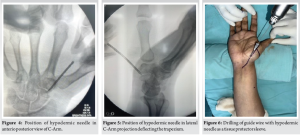

The another big advantage of this needle is to deflect the trapezium [Fig 1-5] on the dorsal side to get a better axis of drilling along the length of the scaphoid. Taking advantage of the sturdy nature of the needle, it is used to push the trapezium a little away to get a good central entry point, which is the most important step of the surgery.

The patient is positioned as per the fracture type – commonly supine with the hand on a radiolucent table[Fig. 1]. Under image intensifier guidance, the fracture is reduced closed or with minimal manipulation. The 16-gauge needle is inserted at the desired entry point and advanced toward the fracture site in the required orientation.[Fig. 1,2]

Marking of the long axis of the scaphoid under the image intensifier television in both anterior-posterior and lateral views[Fig. 1,2]. Note a folded sheet over the back of the wrist, causing extension.[Fig. 1]

Insertion of the hypodermic needle along the long axis of the scaphoid, starting at the distal pole of the scaphoid.[Fig. 3,4]

Point of entry in the lateral view. Note the bending of the hypodermic needle while deflecting the trapezium away to get a central trajectory.[Fig. 5]